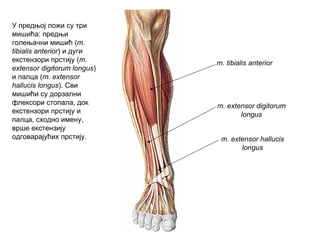

У предњој ложи су три

мишића: предњи

голењачни мишић (m.

tibialis anterior) и дуги

екстензори прстију (m.

extensor digitorum longus)

и палца (m. extensor

hallucis longus). Сви

мишићи су дорзални

флексори стопала, док

екстензори прстију и

палца, сходно имену,

врше екстензију

одговарајућих прстију.